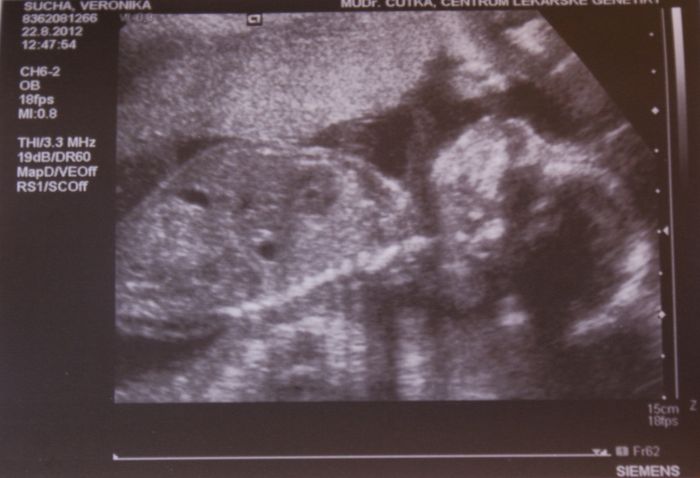

Teda koukám, že se u těch fotek při rozbalení píšou spřeházený názvy, ta první je ze 14.týdne, druhá je focená před chvilkou, moje bříško dnes 20.týden a třetí z UZ ze včera 20.týden mimísko

A jinak je to fakt asi pohodář, protože jak ve 14.týdnu tak včera při UZ měl jednu ruku za hlavou

Sem taky přidám fotečku, ale neni to tam pořádně vidět no...